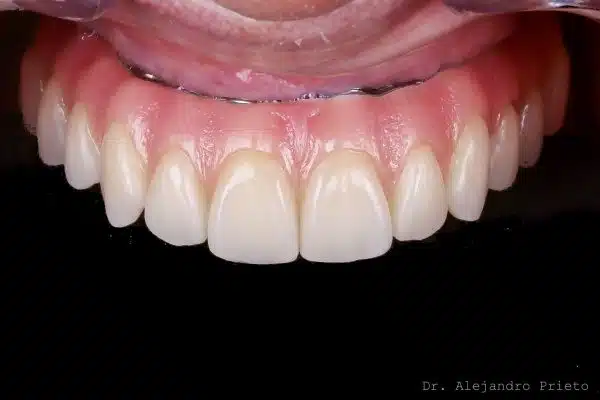

Implantes pterigoideos: antes y después

Los implantes pterigoideos permiten pasar de una situación de edentulismo o prótesis inestables a dientes fijos, incluso en pacientes con atrofia ósea severa.

A continuación se muestran casos reales de implantes pterigoideos antes y después, donde se aprecia la mejora funcional y estética.